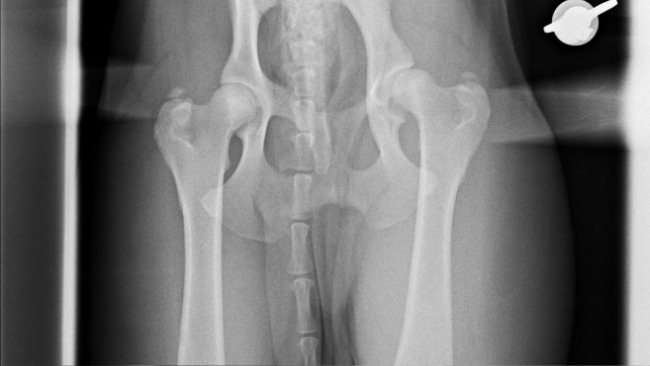

Mój pies ma poważne problemy zdrowotne. Niestety ma on dysplazję stawu biodrowego. Ma bardzo duże problemy z żołądkiem,częste biegunki oraz zdarzają się wymioty oraz dziwny kaszel. Mój pies jest dla mnie bardzo ważny, ponieważ pomaga mi w moich codziennych problemach oraz pomaga mi, kiedy mam ataki paniki. Cierpię na zaburzenie osobowości borderline zaburzenia lękowe, depresje, nerwice lękową, zaburzenia odżywiania oraz aburzenia kontrolowania impulsów. Baks jest ze mną codziennie ,również śpi ze mną dlatego tak bardzo ważne jest dla mnie to, aby wszystko było u niego w porządku. Niestety od jakiegoś czasu mamy z nią coraz więcej problemów. Wydaliśmy już naprawdę dużo pieniędzy na badania, jednak już nie mamy z czego wziąść. Bardzo zależy mi na tym, aby uzbierać sumę wystarczającą na dojechanie do gastrologa, aby zrobić gastroskopię, kolonoskopię, aby zrobić kolejny rentgen stawu biodrowego, aby w razie czego opłacić chociaż połowę operacji.